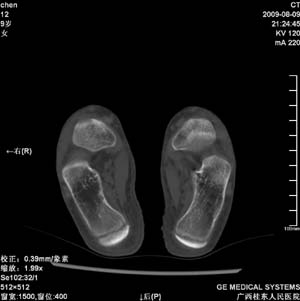

标题: PED2867:右侧内踝肿胀,骨质改变,请各位老师会诊 [打印本页]

标题: PED2867:右侧内踝肿胀,骨质改变,请各位老师会诊

九岁小朋友,近期左侧内踝疼痛,局部肿胀,平时无特殊,近期经常溜干冰

对不起,是右侧内踝肿胀

双踝关节骨质及发育未见异常。